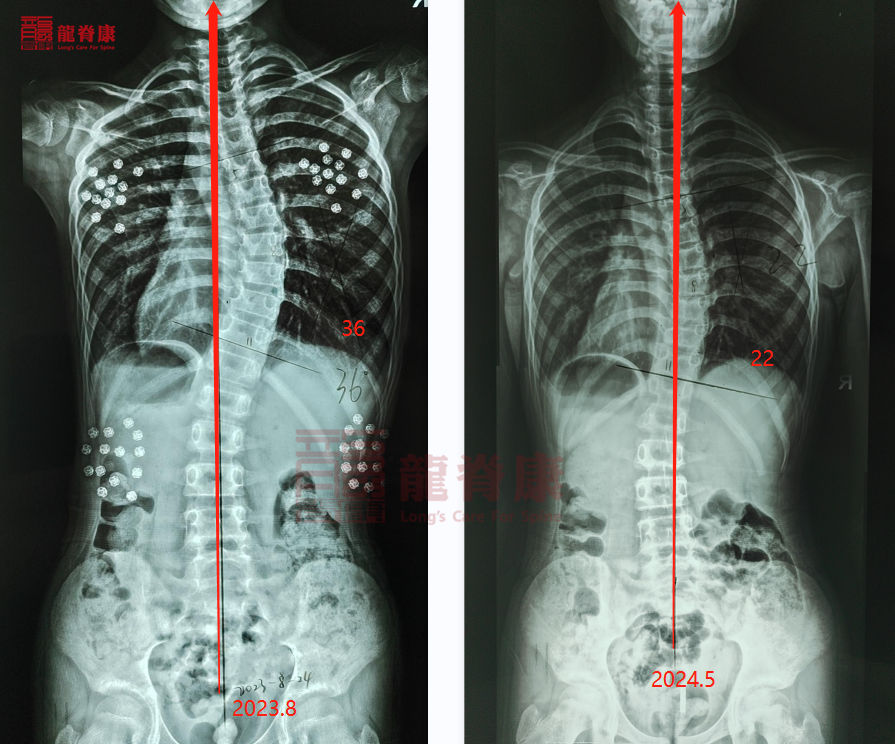

对于儿童和青少年患者,由于他们的骨骼尚未完全发育成熟,因此早期发现和及时治疗往往能够取得更好的效果。通过一系列的保守治疗措施,如佩戴矫形支具、进行特定的体操锻炼等,有可能控制侧弯的进展,并逐步矫正脊柱的形态。然而,对于重度侧弯且影响日常生活的患者来说,手术治疗往往是不可避免的。手术的主要目的是尽可能恢复脊柱的正常生理曲度,提高脊柱的活动功能,从而改善患者的生活质量。但需要注意的是,手术治疗并不能保证完全治愈脊柱侧弯。术后,患者还需要进行持续的康复训练和定期复查,以确保手术效果并预防侧弯的复发。患者的身体基本情况和治疗方式,也是影响治疗效果的重要因素。例如,患者的营养状况、心理状态以及是否伴有其他并发症等都会影响治疗的效果。因此,在治疗过程中,医生会根据患者的具体情况制定个性化的治疗方案,并密切关注患者的病情变化。

脊柱侧弯一旦确诊,基本上是不可能自愈的。如果放任不管或者采取不专业的干预措施,侧弯的角度可能会逐渐增大,导致更严重的后果。